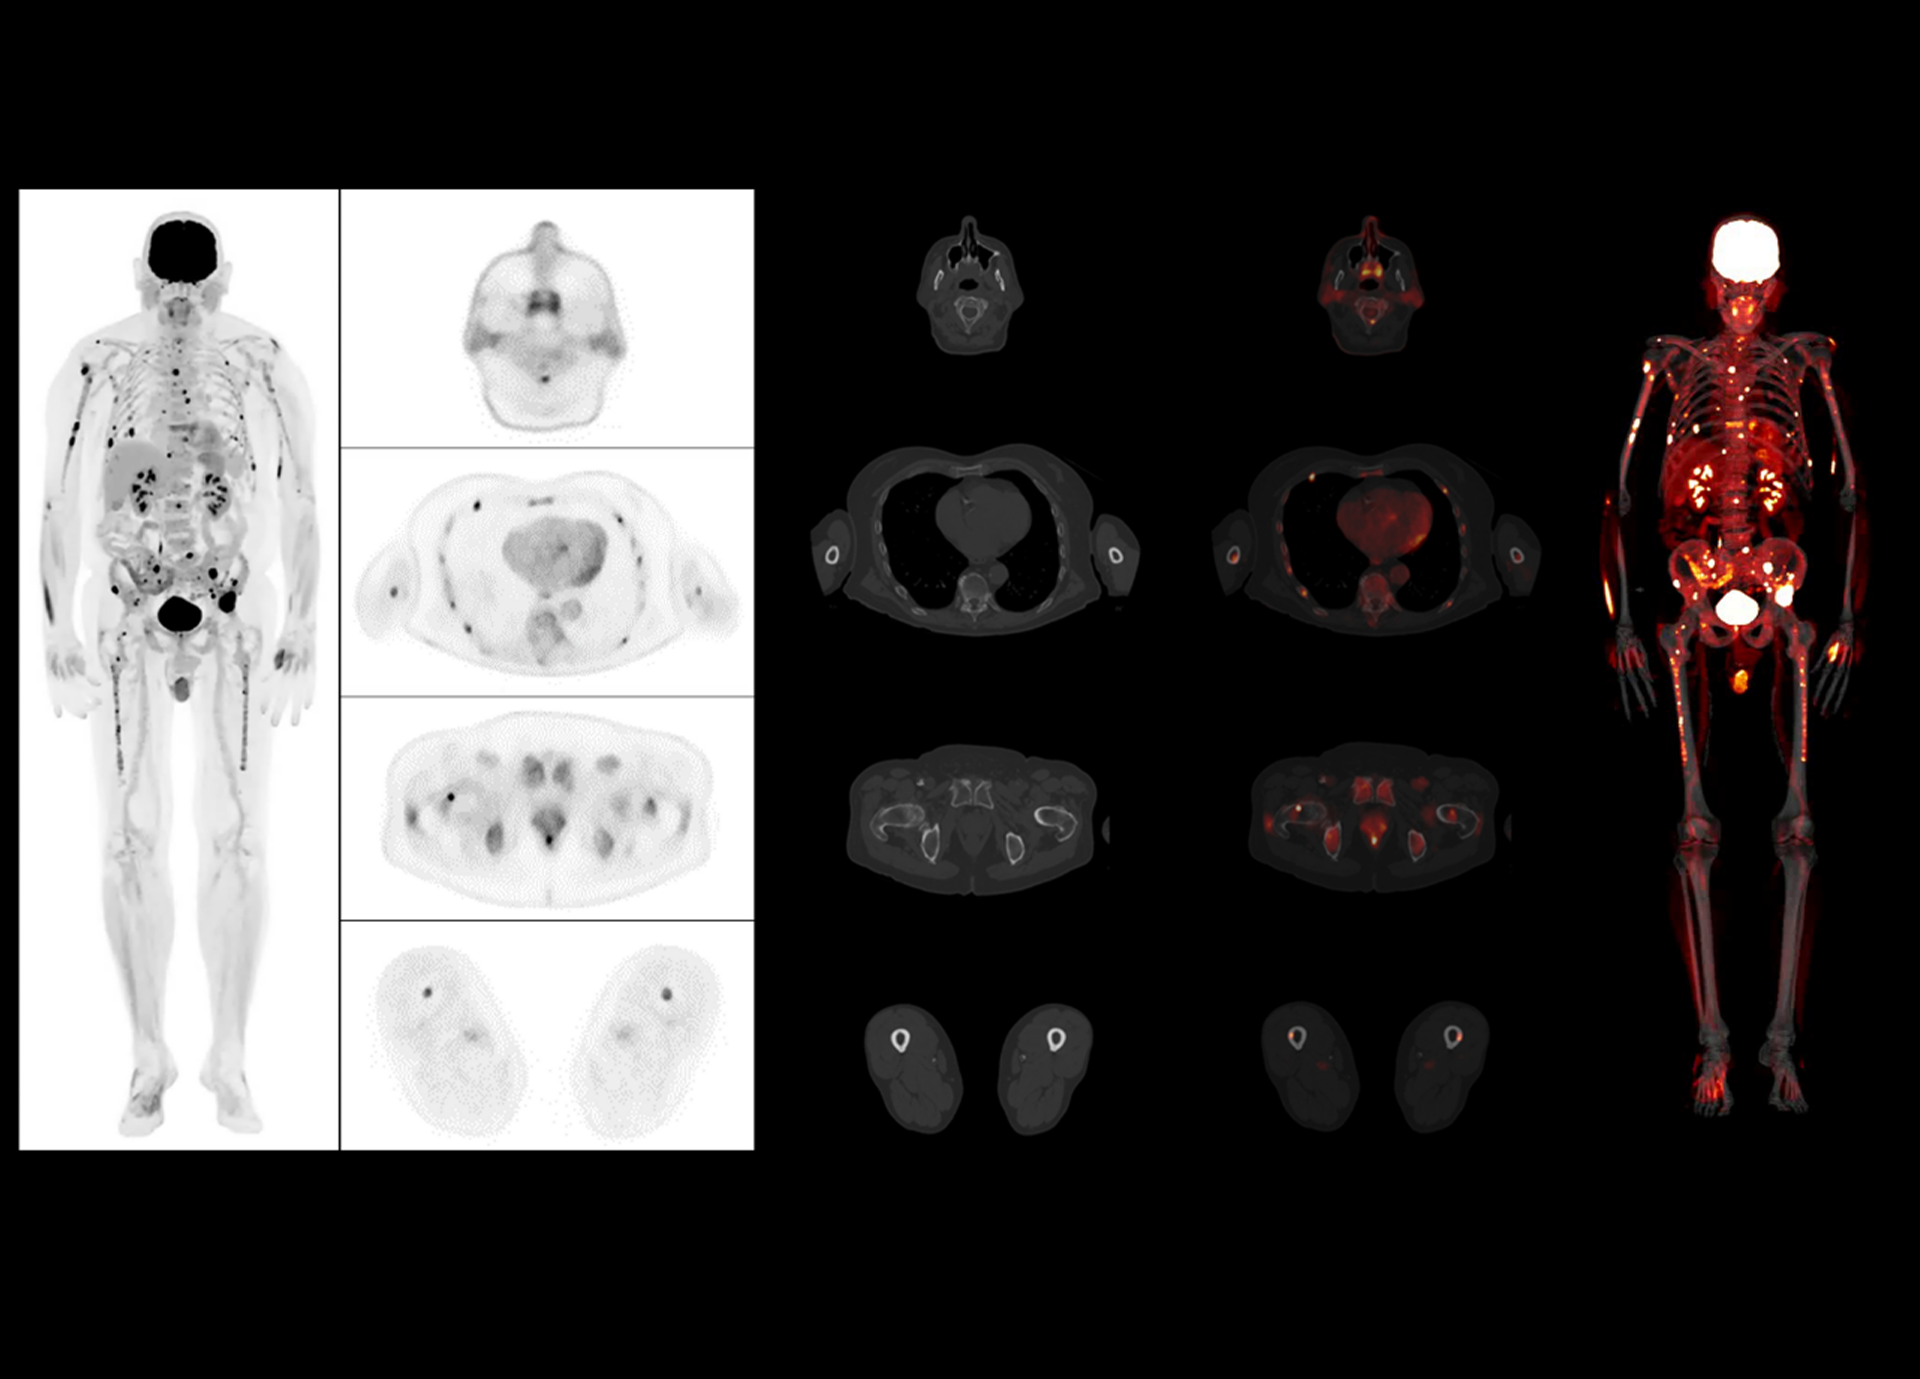

Leading TOF resolution that boosts small lesion detectability and clarity.

181 cps/kBq and more¹

High effective sensitivity that benefits from TOF gain leverages better diagnostic accuracy under low dose usage and fast scan time.